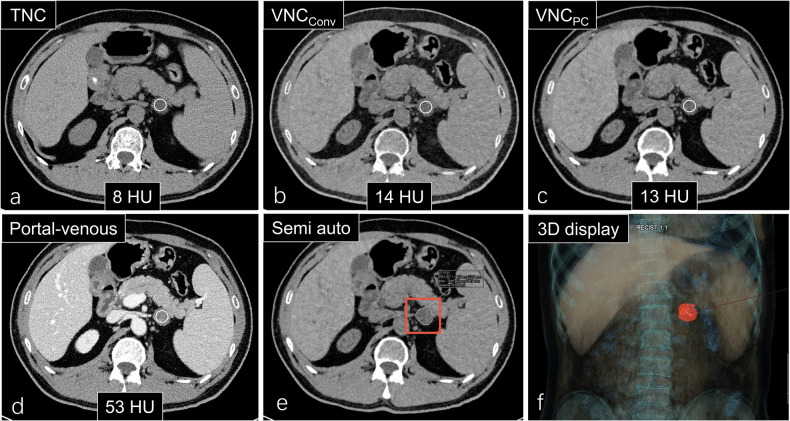

Materials and methods: Participants with adrenal masses who underwent unenhanced and portal venous phase PCCT were prospectively included. Portal-venous phase images were reconstructed using conventional VNC (VNCConv) and PureCalcium VNC (VNCPC). We measured two-dimensional (2D) attenuation of adrenal masses at their largest slice on true noncontrast (TNC), VNCConv, and VNCPC images. Three-dimensional (3D) attenuation and radiomic features of adrenal masses were semiautomatically extracted. These parameters were statistically compared, and diagnostic performance for adenomas was evaluated.

Results: The study included 54 participants (27 females, mean age 45.3 years) with 68 adrenal lesions. Attenuation values on VNC were higher than those on TNC. TNC, VNCConv, and VNCPC attenuation values did not differ between 2D and 3D measurements. The intraclass correlation coefficients of first-order, shape, and texture features between TNC and VNC were 0.671, 0.822, and 0.616, respectively. The sensitivity and specificity of the proposed thresholds (VNCConv 25 HU, VNCPC 20 HU) were higher than those of the previously established threshold of 10 HU in diagnosing adenomas. There was no significant difference between VNCConv and VNCPC in diagnosing adenomas (area under the receiver operating characteristic curve: 0.841 versus 0.838, p = 0.873).